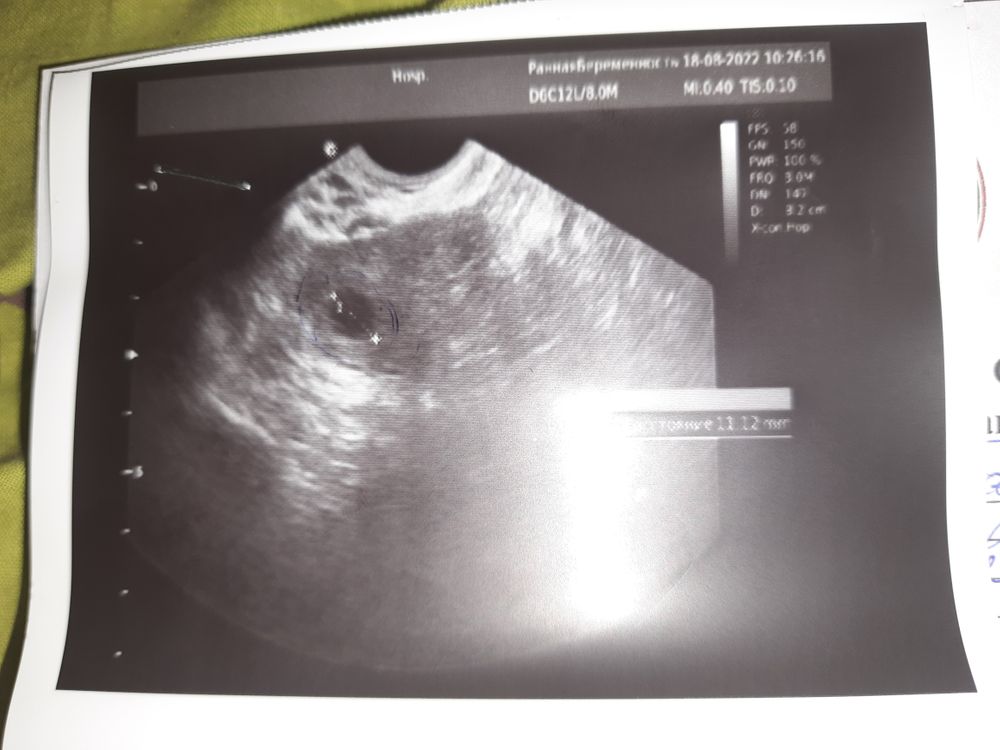

На УЗИ есть пара снимков,где что-то похожее на микро ПЯ. Конечно,лучше на УЗИ в 5-6 недель